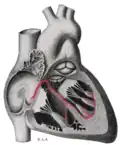

Sinoatrial node shown at 1. The rest of the conduction system of the heart is shown in blue.